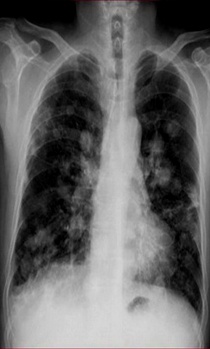

滿肺可見“滿天星”,根據公式診斷肺轉移瘤